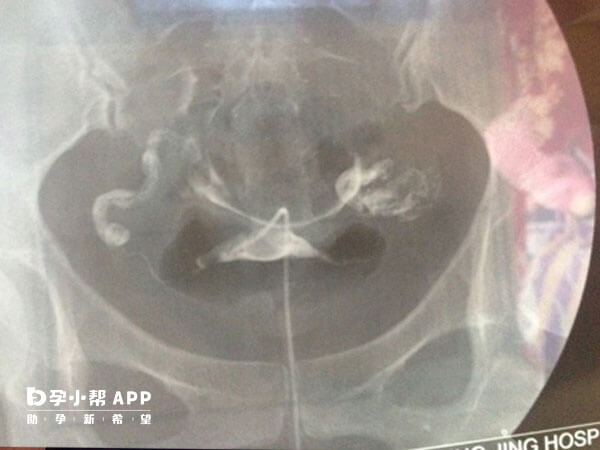

输卵管增粗是指输卵管的直径超出了正常范围,通常提示输卵管解剖形态和生理功能发生病理性改变。一般存在这类情况可能会对胚胎移植造成一定的影响,对此感兴趣的可以参考下列内容了解。

输卵管增粗引起的轻度炎症或粘连,可能不影响胚胎移植,而且若另一侧输卵管正常,仍有成功怀孕的几率,但是其成功率可能降低;

若增粗由炎症或积水引起(如输卵管积水),可能通过反流液体改变宫腔环境,降低胚胎着床率;

积水中的炎性因子可能干扰胚胎发育,增加流产风险。

输卵管增粗伴管腔狭窄时,可能增加宫外孕概率,但试管婴儿(IVF)技术可绕过输卵管,直接移植胚胎至子宫,显著降低此风险。